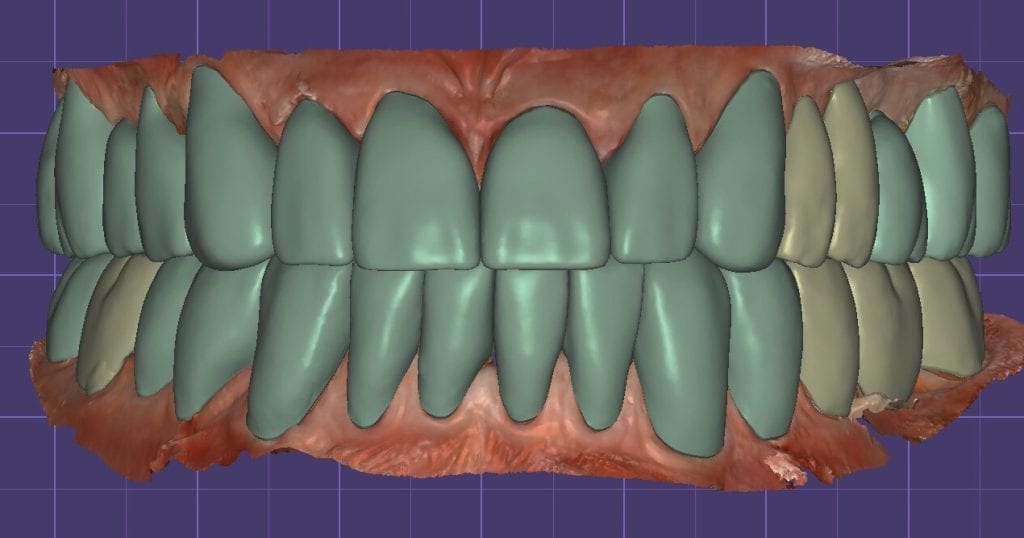

The digital models were then imported into a third party software where a library of tooth morphologies are available for the clinician to choose from.

Once the appropriate library is chosen, the digital wax ups are performed. In the subsequent photos you can see the transparent overlay of the wax-ups to the original position of the existing dentition